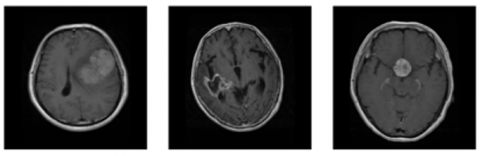

The second data set used in this study is a collection of whole brain volume MR images initially presented by Marcus et al. [39]. This dataset was primarily designed to investigate dementia in elders. It comprises longitudinal images of 372 sets obtained from 100 aged subjects among 50 and 93 years. The sample data set image is shown in Figure 4.

Figure 4. Data set image